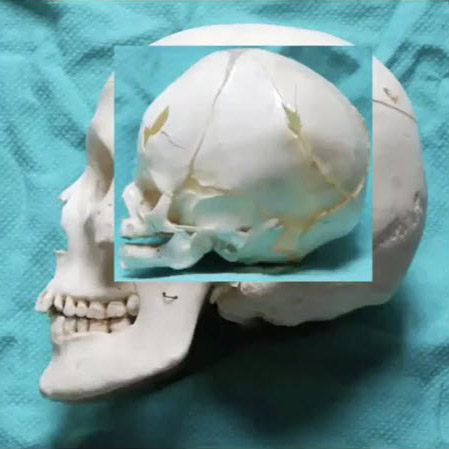

When we look at the pediatric facial skeleton, it's different to the adult skeleton. The pediatric skeleton is primarily cranium, with a small facial volume. It's an 8:1 ratio compared to 2:1 in adults. We’re born without sinuses then start developing them: the maxillary sinus around five to six years of age, and the frontal sinuses again around six to eight. Then, tooth eruption happens around six to eight, which guides vertical growth of our mandible and maxilla. By seven to eight years of age, our cranium and our orbits are about 80% to 90% of the adult size, so an injury at that stage is going to cause less growth disturbance than an injury at six months of age, before things have developed.

The injuries that happen that are low velocity tend to be in the upper face, because these are bigger parts of the face. In terms of the midface, we're talking about the zygomatic arch, the zygoma, maybe the NOE or the nose primarily. They tend to be greenstick injuries. The bones are more cancellous than cortical, so the bone is softer, more "rubbery". The fragments are large and there's less comminution. Again, the displacement is limited, and they tend to be isolated injuries.